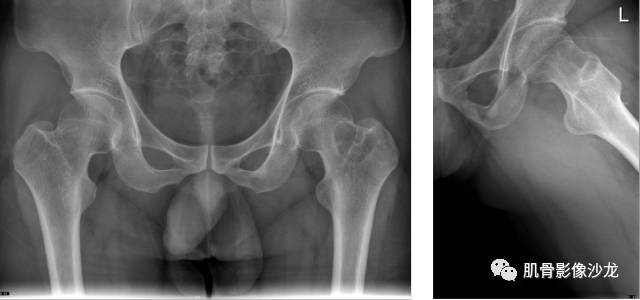

主诉:左髋疼痛1月余

现病史:患者1月余前无明显诱因出现左髋部疼痛,无明显活动受限,当地医院行X线检查,提示左股骨颈异常密度。遂来我院就诊。

既往史:曾患乙型肝炎,未正规治疗,目前无症状。

葛英霖 20:5 4 常规纤维类的多一些,冠状位没有看到明显脂肪。纤维结构不良、纤维组织细胞瘤、软粘纤之类。

夏威夷的风 20:55 大方向纤维类病变

夏威夷的风 20:58 强化渐进性强化吧 边界清晰 里面也见线状低信号

飞鹰行动 21:01 良性纤维组织细胞瘤内部可以有少量脂肪

X(CT、MR)战警 21:01 泡沫细胞被吞噬后形成脂肪信号, bfh可以有脂肪条带样改变

Echo 21:04 总之这例就是各位老师说的硬化边明显,没有软组织肿块,没有侵犯,考虑良性病变,增强渐进性强化,所以考虑BFH